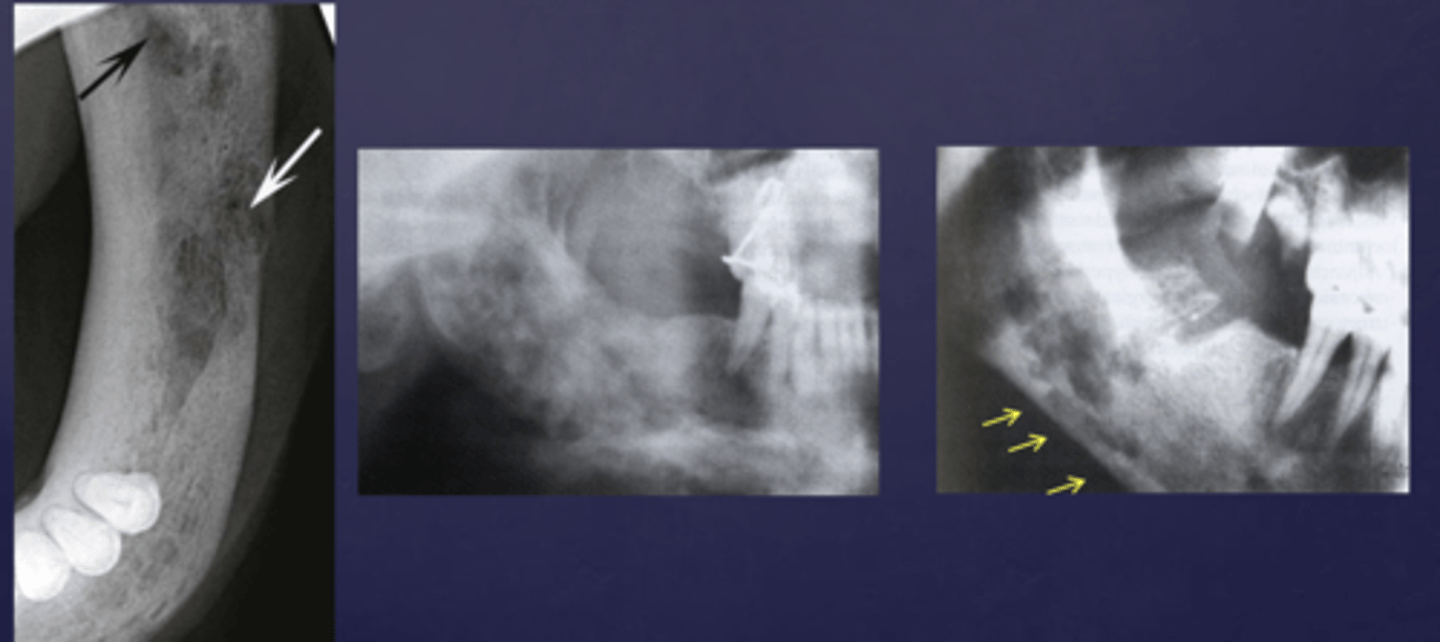

These arrows are pointing at what?

moth-eaten appearance of acute osteomyelitis

The moth eaten appearance is associated with what?

acute osteomyelitis, mixed radiolucent/radiopaque areas

What is the black arrow pointing at?

sequestrae

What is the white arrow pointing at?

periosteal reaction

periosteal reaction (increased bone density)

sequestra

What phase of osteomyelitis does this show?

acute (multiple sequestrae)